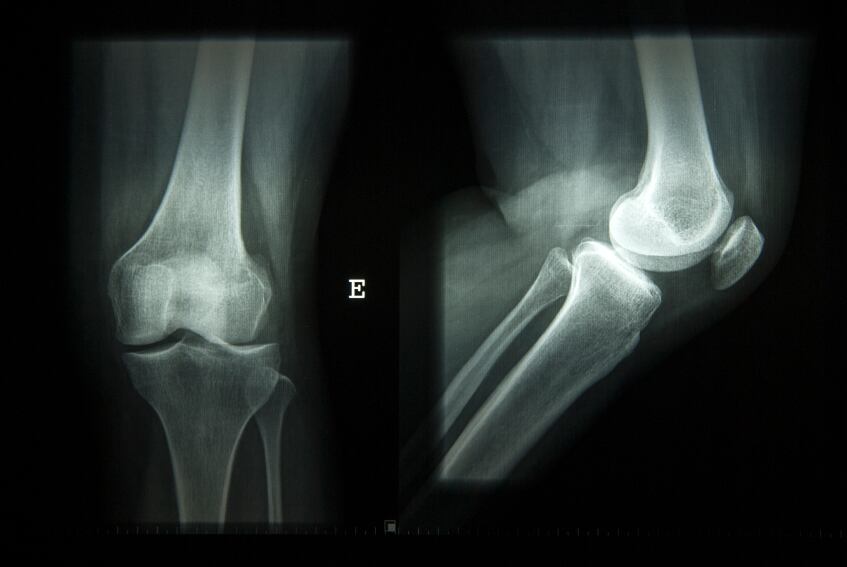

“If we rewind 100 years or so, one of the micronutrients of most concern in the UK was vitamin D, a lack of which caused widespread occurrence of rickets amongst children,” the food industry-backed charity wrote in Nutrition Bulletin.

“This easily preventable bone disease was virtually eradicated by the 1950s with a reduction in atmospheric pollution, improvements in diet in the post-war period, alongside mandatory fortification of margarine and use of cod liver oil supplements but its re-emergence has helped to put vitamin D back in the public health spotlight.”

Indeed vitamin D has only really hit headlines again with the supposed re-emergence of the 'functional health outcome' of rickets.

According to the UK’s National Health Service (NHS) the number of rickets cases was still relatively small with less than 700 cases diagnosed in English hospitals in 2013-14.

BNF says the risk of poor musculoskeletal health is increased at serum 25(OH)D concentrations below 25 nmol per litre.

In the UK, one in five people have serum levels below this level, ranging from 7.5% in 1.5-3 year olds to 12.3% of girls and 15.6% of boys aged four to ten years, 19.7% of boys and 24.4% of girls aged 11-18 years and 24% of men and 21.7% of women aged 19-64 years.